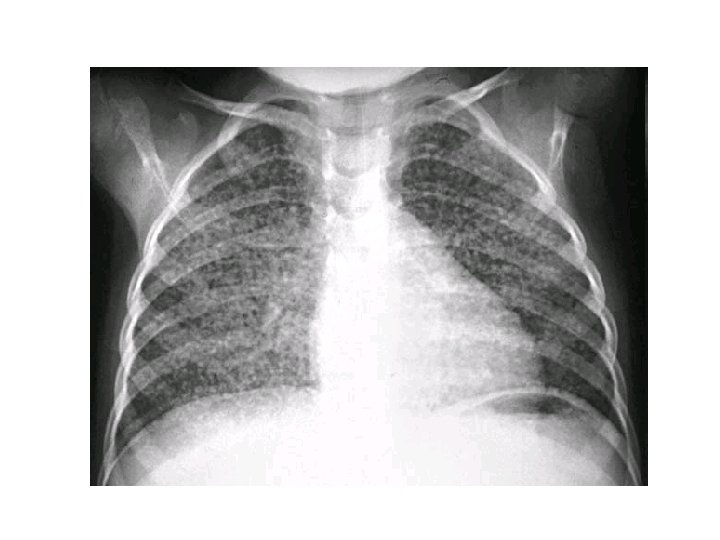

Diagnosis • Obtain HIV in all patients with TB • CXR – – – may show a patchy nodular infiltrate upper-lobe involvement is most common in any part of the lung cavity: indicates advanced infection • high bacterial load • Miliary TB: appearance of numerous small nodular lesions that resemble millet seeds on CXR